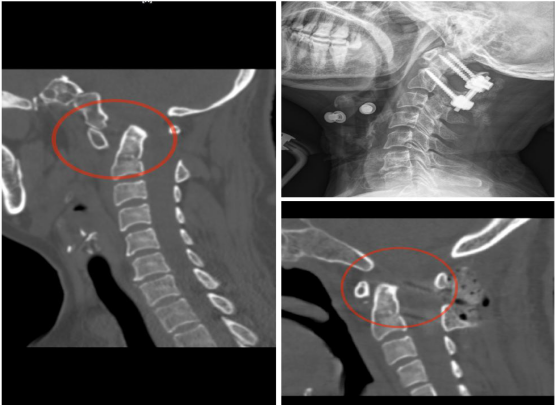

如齿状突骨折、寰枢椎骨折(脱位)、寰枕畸形等,上颈椎失稳可引起严重的脊髓功能障碍。上颈椎前路或后路手术骨折复位固定,重建脊柱稳定性,解除脊髓压迫。

注:手术前CT示齿状突骨折,手术予微创前路中空加压螺钉内固定,术后照片显示骨折复位满意。

注:手术前CT示寰枢椎脱位,椎管狭窄,手术予后路寰枢椎螺钉内固定,术后照片显示骨折复位满意。